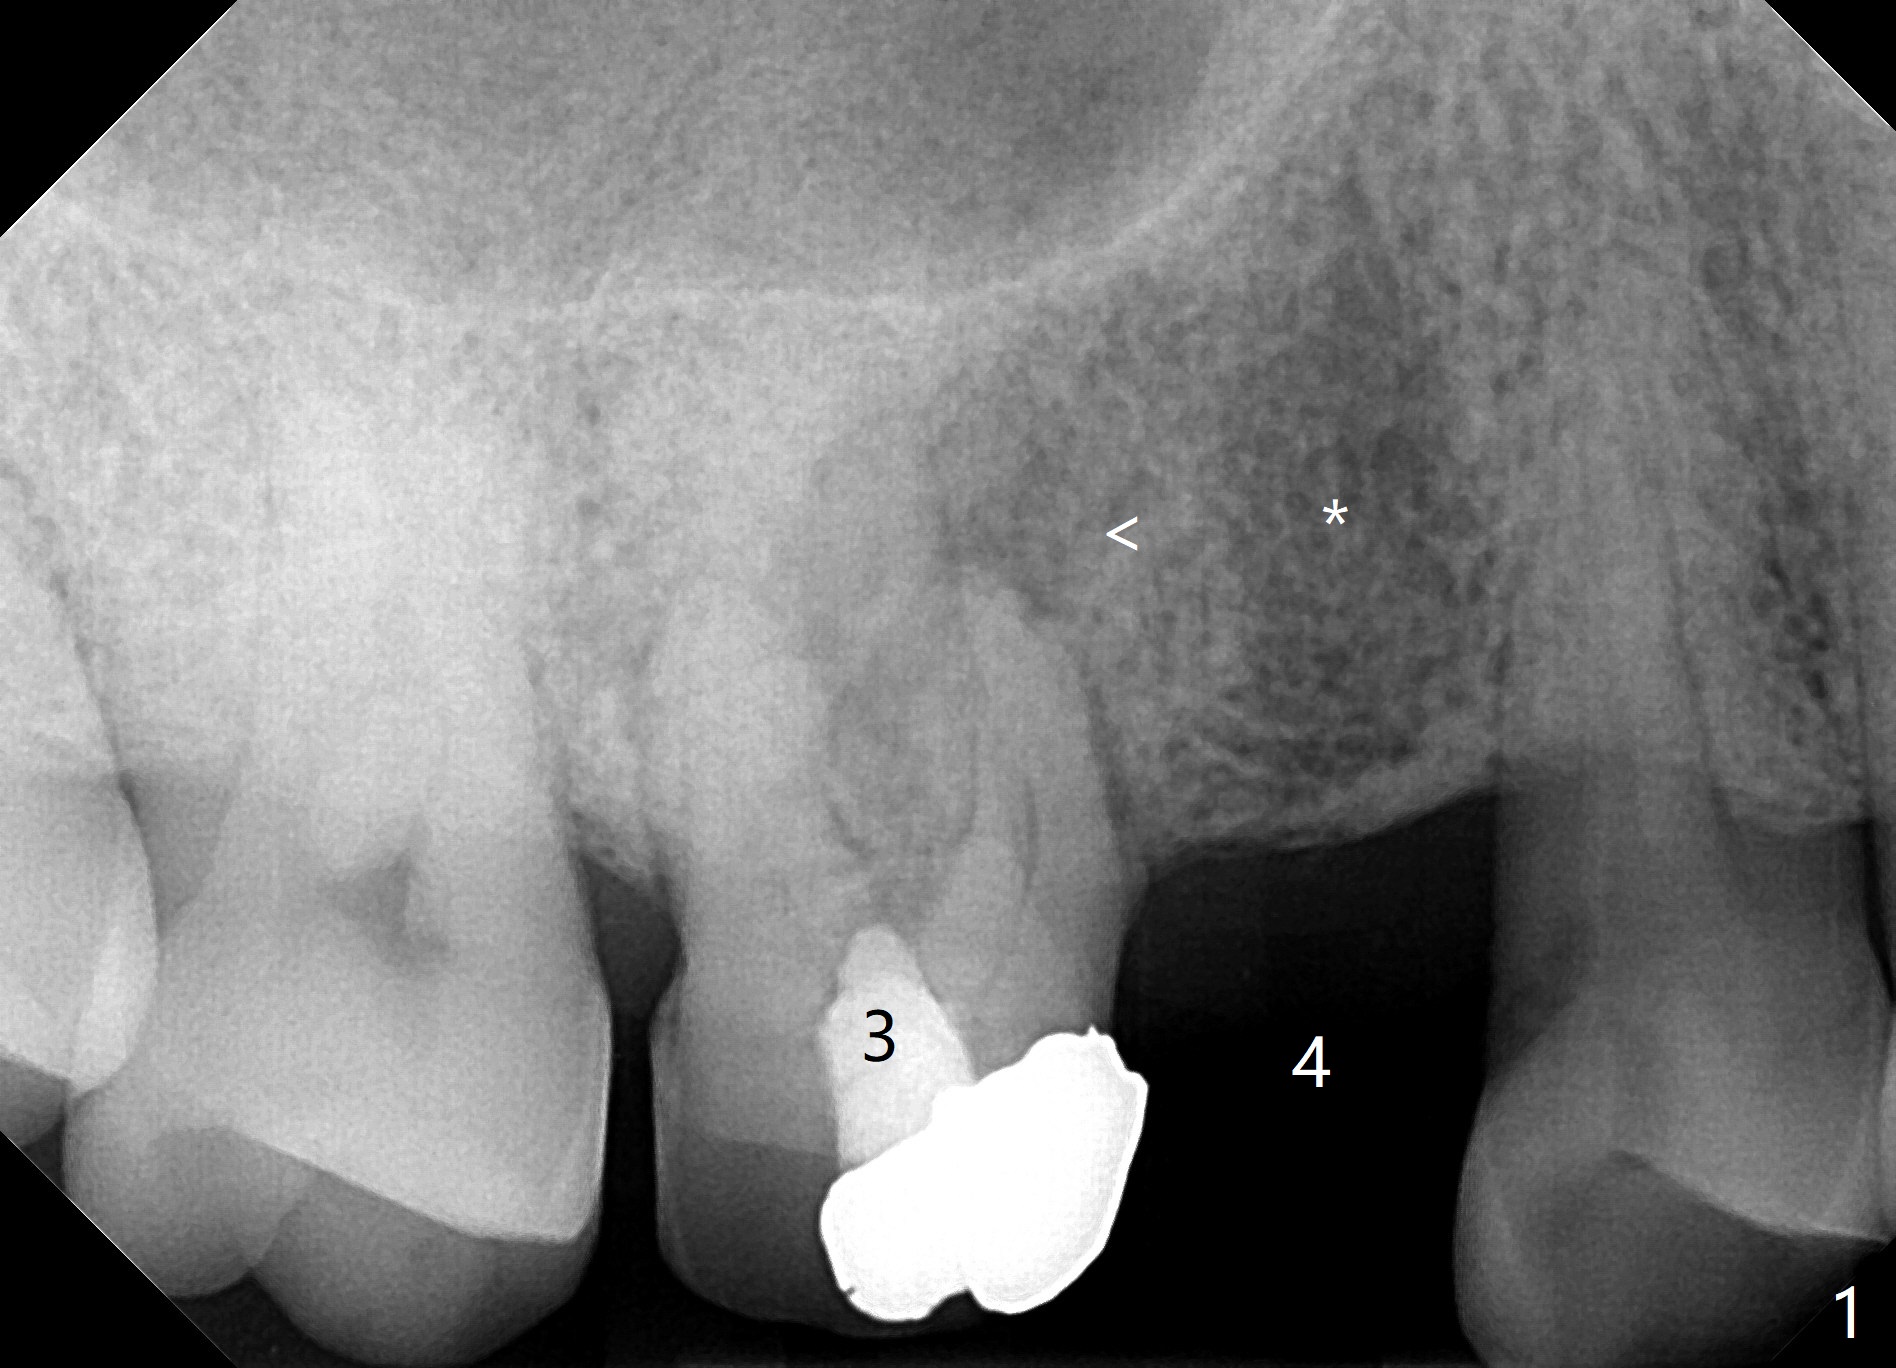

A 67-year-old man used to have a 3/4 cantilever bridge, which is dislodged (Fig.1). The anchor tooth has a buccal fistula with apparent furca perforation and mesiobuccal periapical radiolucency (<). Prior to extraction, the tooth will be used as a surgical guide for implant placement at #4 (Fig.2). Since the bone density at #4 seems to be low (*), bone expander kit will be used.